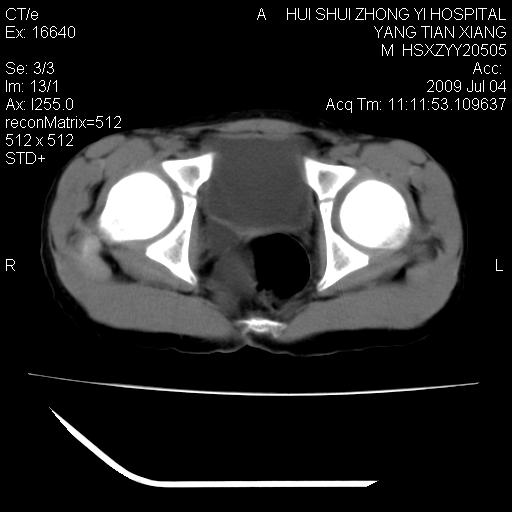

肝右叶胆管内见条状高密度影,脾脏增大,双肾上腺无异常;右肾正常结构消失,其实质内见类圆形低密度灶,ct值范围0-6hu,界清,右输尿管全程伴行多发低密度灶,界清,膀胱壁增厚,腹盆腔未见确切肿大淋巴结。

考虑:1、肝内多发胆管结石并肝内胆管扩张。2、右肾、输尿管多发脂肪瘤,多发平滑肌瘤?建议ct增强检查。4、膀胱壁增厚。

右侧巨输尿管可能。

膀胱壁增厚。

2、右侧巨输尿管并右肾积水可能性大。

右侧巨输尿管并神谕积水,左肾代偿性肥大,脾大,肝内胆管多发结石并胆管扩张。